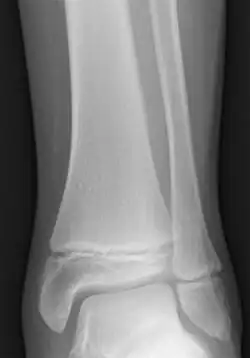

Epiphyseal plate

The epiphyseal plate, epiphysial plate, physis, or growth plate is a hyaline cartilage plate in the metaphysis at each end of a long bone. It is the part of a long bone where new bone growth takes place; that is, the whole bone is alive, with maintenance remodeling throughout its existing bone tissue, but the growth plate is the place where the long bone grows longer (adds length).

The plate is only found in children and adolescents; in adults, who have stopped growing, the plate is replaced by an epiphyseal line. This replacement is known as epiphyseal closure or growth plate fusion. Complete fusion can occur as early as 12 for girls (with the most common being 14–15 years for girls) and as early as 14 for boys (with the most common being 15–17 years for boys).[1][2][3][4][5]

Salter–Harris fractures are fractures involving epiphyseal plates and hence tend to interfere with growth, height or physiologic functions.[12]